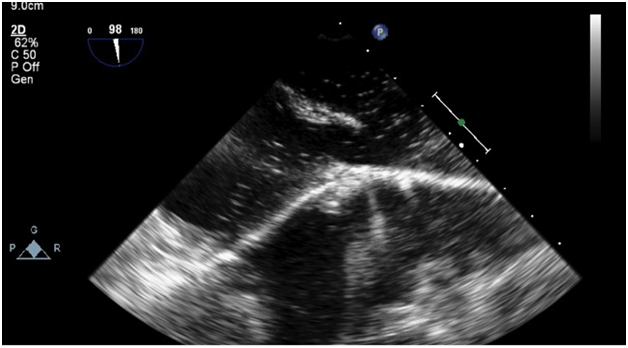

The patient was started on an intravenous infusion of Mannitol and 3% saline for impending herniation. His mental status gradually worsened in the emergency department and was intubated for airway protection. Digital subtraction angiography was subsequently done clearly demonstrating the presence of a large choroidal type vein of Galen malformation with the particular features illustrated in (Figures 2a & 2b). 24hrs after admission the patient became febrile. Blood cultures were positive for enterobacter. Transesophageal echocardiogram performed to evaluate for the presence of valvular vegetations revealed the presence of a large sinus venosus defect (11mm) with a large right to left shunt demonstrated with agitated saline contrast injection and color Doppler (Figures 3a & 3b). An anomalous right superior pulmonary vein draining into the SVC, which has an association with sinus venosus ASD, was also detected.

Figure 3A TEE images showing positive bubble study.

Figure 3B Color Doppler consistent with Sinus Venosus ASD with bidirectional shunt.